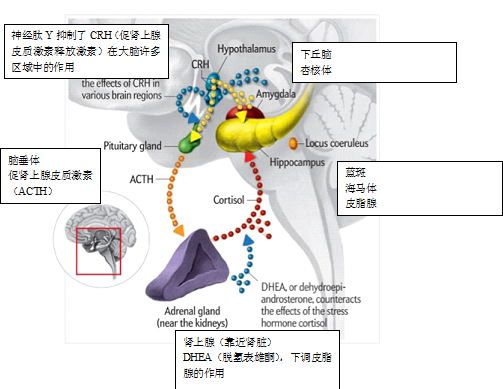

而对大脑的质化描绘会是这样吗?。

图片来自2011年3月《科学美国人》“勇气的神经科学”一文,作者:Gray Stix,插图作者:Jen Christiansen。

图片来自2013年9月《科学美国人》“食物上瘾”一文,作者:Paul J. Kenny,插图作者:Bryan Christie。